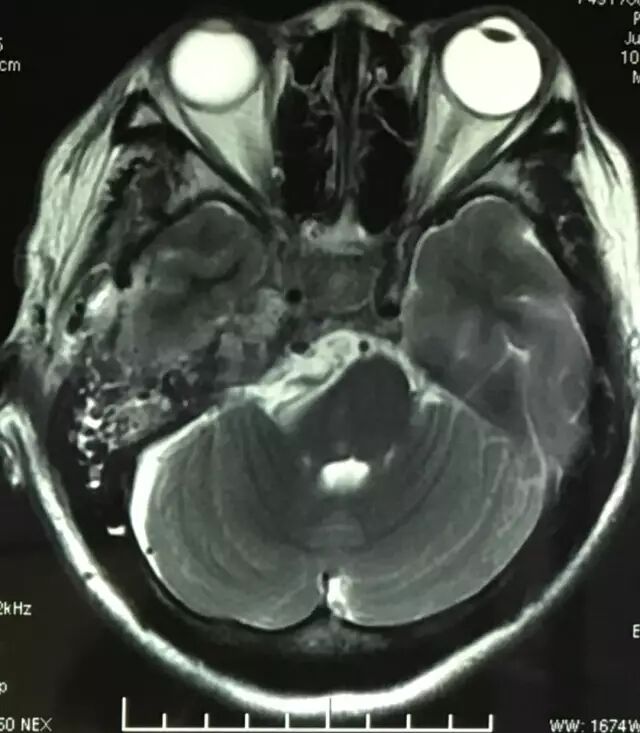

查体:神清语利,双瞳等,光反应灵敏,右侧面部浅感觉减退,行走不稳,四肢肌力基本正常。核磁共振检查见右侧岩斜区肿瘤,考虑岩斜脑膜瘤。

肿瘤强化明显,部分侵入海绵窦。